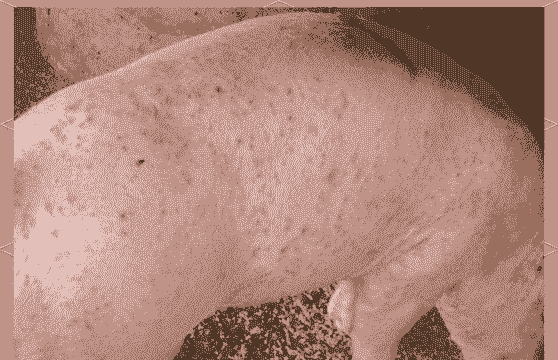

由圆环病毒引起的多发生于12~14周龄仔猪的传染病,以皮肤出现红色丘疹为主,伴有厌食、呆滞、苍白、发热、结膜炎、呼吸困难、腹泻、消瘦等症状。

一种免疫抑制性的皮肤性疾病,在夏季非常多见,表现为猪只体表的不同部位出现数量不等、大小不一的粉红色或红紫色斑点。